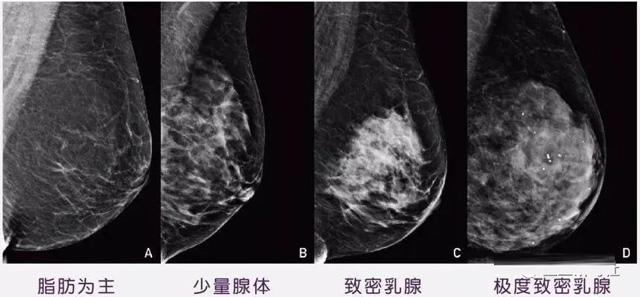

女性乳腺的自我檢查,特別是注意有小結節,腫塊,乳頭有液體滲出情況,需要通過乳腺DR,X光線,磁共振等影像技術檢查。胸的大小跟乳腺癌沒多大關系,乳腺的密度大發病率高一些,胸小脂肪少致密性大。更容易乳腺癌。這個還不能通過自我檢查來確認。致密乳腺組織看上去是白色或淺灰色需要通過乳腺X射線檢查。